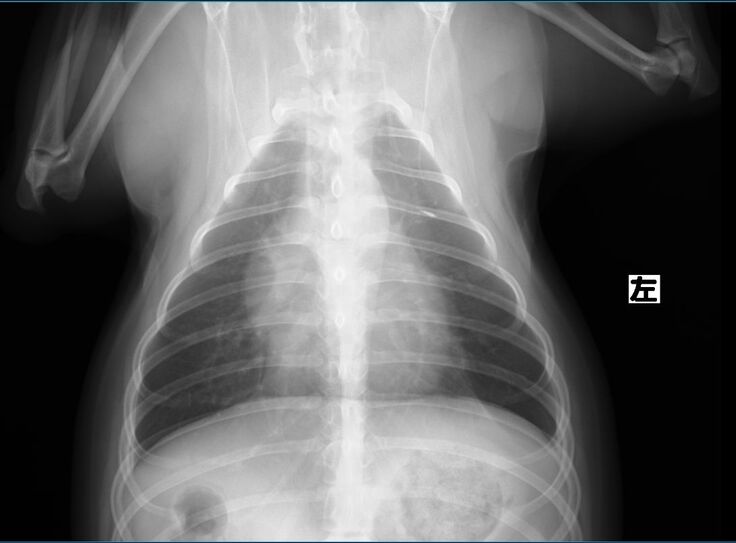

以前より下部尿路疾患で尿路結石を持っているチョコですが、膀胱にある結石が大きくなり膀胱を痛めて膀胱炎を頻繁に発症するようになりました。

膀胱炎から炎症が全身に、更には脾臓の腫瘍が確認されました。

膀胱炎の資料をご覧ください。

検査結果もかなりの異常さが分かると思います。

現在9歳のチョコですが、脾臓はいずれ摘出した方が良いと獣医師より指摘されております。まだ若いので悪性の可能性は低いと言われています。また、結石も同時に摘出をした方が良いと。

検査の結果、脾臓肥大が限界近くの爆発寸前になっていることが判明しました。

脾臓は4センチまでなってるから、いつ破裂してもおかしくない状況。